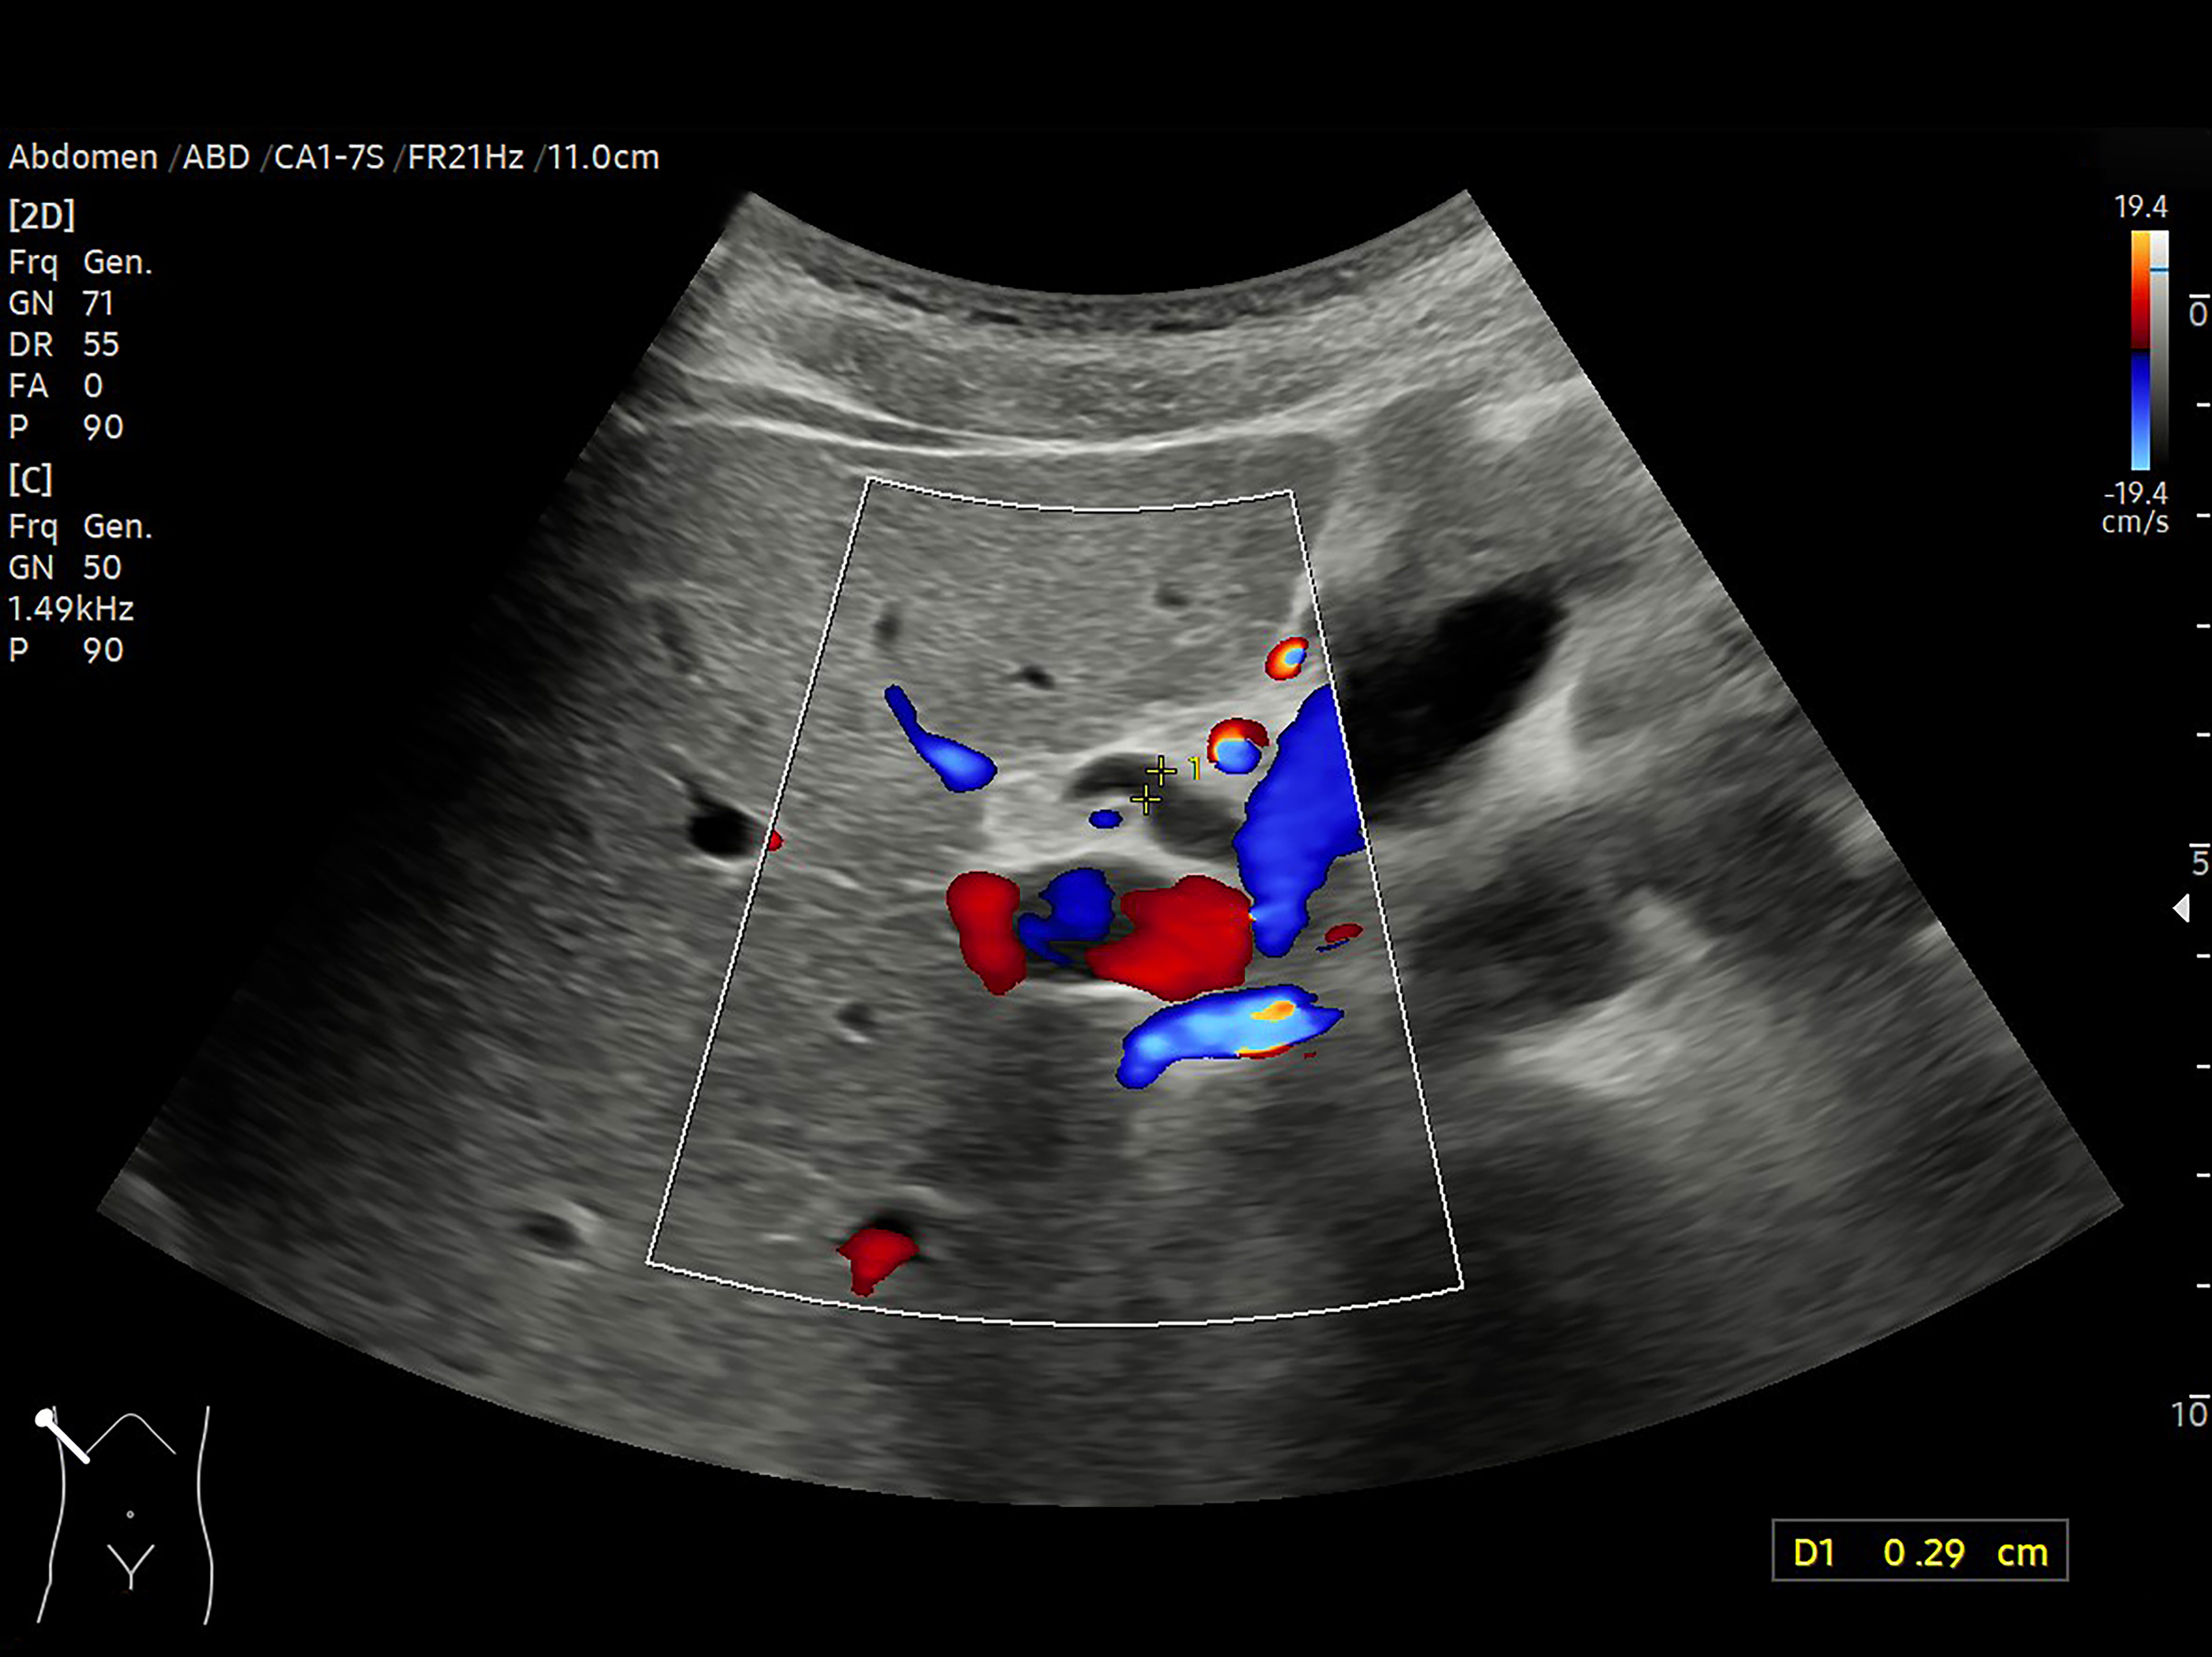

With the dissemination of small, portable, ultrasound devices [or SPUDs], it seems that it is every house-officer’s dream to own the ability and wherewithal to place an ultrasound probe on a patient and find something meaningful; but what exactly is inferior vena cava [IVC] collapse with inspiration telling us?

The reason IVC collapse occurs is that a Starling Resistor is generated — when the pressure within a distensible tube drops below the pressure without the tube. It seems straightforward, therefore, that collapse depends on two competing pressures:

The pressure within the IVC which is related to the central venous pressure [CVP, i.e. the right atrial pressure barring any caval obstruction] and

The pressure within the abdominal cavity.

Collapse of the IVC will be facilitated by a diminution of 1.], an augmentation of 2.], or a combination of both. Addressing each of these forces in turn:

2. Pressure within the Abdominal Cavity

Complicating matters is the increase in abdominal pressure which facilitates IVC collapse. Because positive end-expiratory pressure, intra-abdominal hypertension and breathing pattern all affect the degree of abdominal pressurization [9-12], IVC collapse can be confounded. Thus, inspiratory IVC collapse tells us that the CVP is falling below the intra-abdominal pressure. If there is no pathogenic or iatrogenic pressurization of the abdomen [e.g. PEEP, auto-PEEP, ascites], and inspiration is not stressed [e.g. dyspnea, breathing through an endotracheal tube], then IVC collapse tells us that the CVP is low. The clinician must then understand that a low CVP may be the result of: